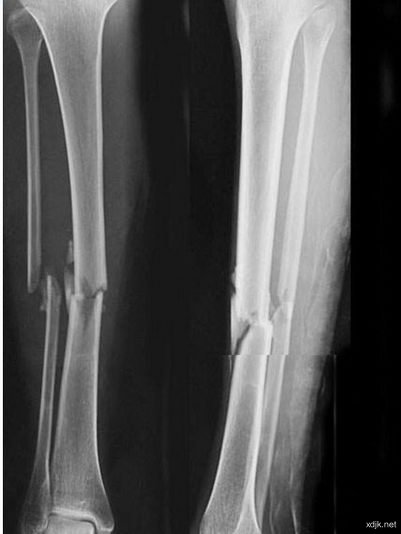

3、徐瑞波,男,68岁,衡水冀州区门庄乡西徐家庄村人,电话;0318*****25,因车祸造成左腿胫骨两处,腓骨一处中段粉碎性骨折,三年来骨痂只有极少部分连接,多处求医问药无效。患者2015年1月14日来诊,望:病人的左小腿皮肤全部变为黑色;问:有无夜间疼痛,答有空心疼感不是太严重;从而得知其骨腔内瘀血斑已经形成,不久便会骨内坏死,面临的必是被截肢的厄运,医院也建议截肢。病人不忍心面对被截肢后的生活,所以苦求于我,我当时也没有完全把握能治好,所以商议试治四周,不见好转立即停药,商定后开始治疗,治疗三周皮肤开始退去黑色变为嫩色,有了好转迹象,治疗七周黑色的皮肤完全变得红润,除一小块约两公分之处没有变好,片子上显示是植假骨的位置,其余完全长好,骨痂也都长好了,这也是我的医疗奇迹,把将要截肢的病人真的治好了。这也是我内心最为喜悦的一例。

4、金汉华,男,48岁,电话;138*****815,江苏海安县曲塘镇人,胫骨骨折6年骨痂不长,曾经做过两次清创术,多处求药均无效,2015年8月26日与我取得联系,我怕时间太长了,断骨腔内淤血坏死,怕有麻烦,病人苦苦哀求,不然就要截肢,只好说定治不好不承担责任,治疗两周不见效果立即停药,如见效治疗七周,如此用药治疗七周病人拍片检查,骨痂完全长好了。这是骨痂不长时间最长的案例。